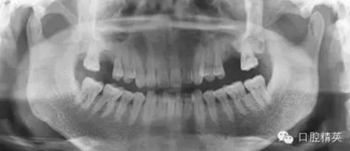

術中切開粘骨膜翻瓣后,用裂鉆打孔3MM術者手明顯落空感,膿血從種植孔流出,術區(qū)于上頜竇交通。膿液排完后縫合粘骨膜瓣,囑術后聯(lián)合應用抗生素,擬炎癥消退半年后復種。

2。中觀察曲斷之所以沒顯示出牙槽骨皮質和松質骨密度明顯異常是因為該患部頰舌冊皮質骨密度正常,中間松質骨密度減低的炎性陰影完全被正常皮質骨影像覆蓋。

3。術前與患者溝通與問診不夠詳盡,沒有問及有無上頜竇炎病史。沒有仔細分析曲斷的左上頜竇的影響與右上頜竇仔細對比。也沒有分析患側上頜竇有無氣室化現(xiàn)象,術者考慮有所不周。